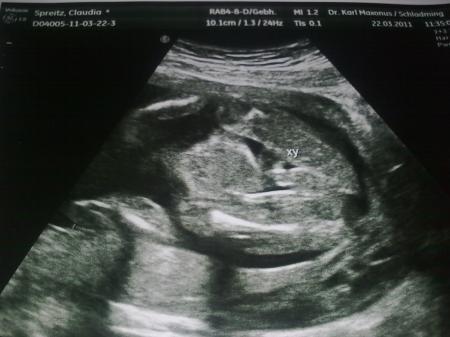

Ich würde auch "Mädchen" sagen, denn zwischen den Beinchen fehlt schon etwas! Ich häng dir mal ein Outingbildchen von meinem kleinen Mann (19.SSW) dran, wo das Zipfelchen eindeutig zu sehen ist (siehe unter XY)! Glg, Claudia

Bild zu